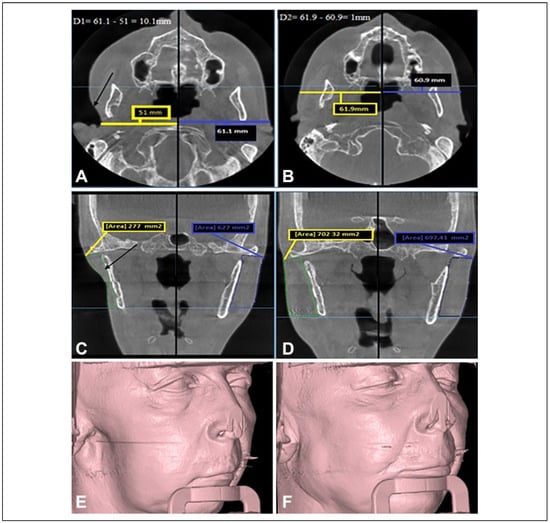

- The measurement of the defect’s depth (DD)Through axial section, a reference point was determined and each half of patient’s face was measured with a linear measurement. The measurements started in the defect side from the deepest point of the soft tissue defect into the midline.The unaffected or normal side was measured at the same horizontal plane with the opposite side from the most lateral soft tissue point into the midline. The difference between these 2 sides represents the defect’s depth (DD).

- Determination of overcorrection in a numeric value (OV)In our study, the overcorrection percentage is 10%-15% from defect’s depth. The defect’s depth (DD) was multiplied by 0.15 to convert the percentage of overcorrection into a numeric value.

- Determination of total graft thickness (TT).The total graft thickness that was needed for each patient was determined by the following formula:Total graft thickness(TT) = defect’s depth(DD) + overcorrection numeric value(OV).The evaluation of patient’s improvements was done through 2 methods:

- Objective evaluation by the clinical examination 1 week, 1 month, 3 months, and 6 months postoperatively. The patients were examined for any sign of infection, liquefaction, rate of graft resorption, and facial symmetry. CBCT scans were used to evaluate linear measurements of augmented region 6 months postoperatively and compare it with the preoperative defect side linear measurements.